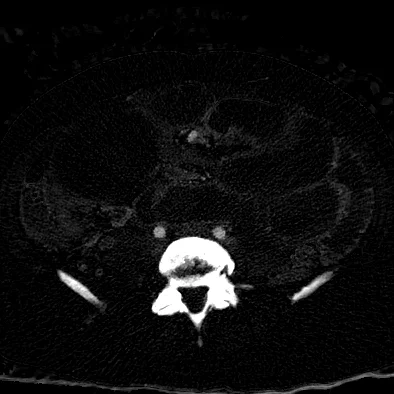

Necrotic fibroid

48 yo F presented with abdominal pain s/p uterine artery embolization for multiple fibroids.

Routine CT shows small bowel obstruction, with 7.8 cm mass near transition point. On spectral analysis, there is no iodine uptake in this mass, and is consistent with necrotic fibroid. Obstruction was managed conservatively, and patient discharged uneventfully.